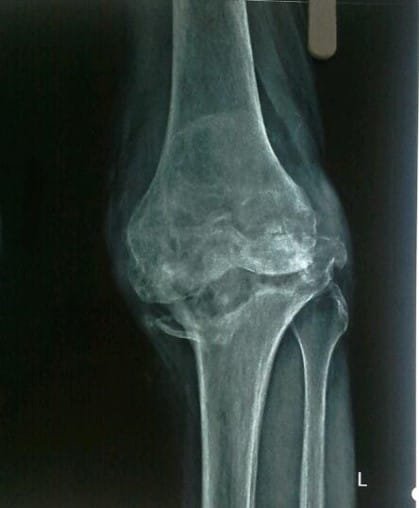

Osteoarthritis (OA) of knee occurs due to wear and tear of cartilage. It is usually due to aging and seen mostly in elderly people. Females usually get affected at slightly earlier age than males. OA can also occur in some cases due to injury in the knee, congenital malformation or due to any other diseases affecting other joints of the body.

It is due to progressive wear and tear leading to loss of cartilage in knee joint. Most commonly, this is due to the aging. In some cases, damage to the cartilage may occur due to rheumatoid and other inflammatory arthritis, trauma, infection, gout, or any other condition affecting knee joint. Those who are over-weight have more chances of developing arthritis in their knees.

Your doctor will do clinical examination of knee joint, hip joint, spine and other joints of your body. X-rays of both knees will be performed. Occasionally, MRI of the Knee joint and few blood investigations may be required as per their underlying problem.